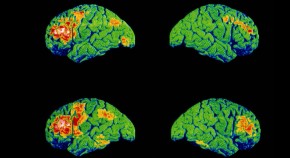

RNA-sequencing analysis of cells in the human cortex enabled identification of diverse cell types, revealing well-conserved architecture and homologous cell types as well as extensive differences when compared with datasets covering the analogous region of the mouse brain.

Whether cell types in the brain have been conserved during evolution is not clear. A comparison of the molecular recipes that define brain cell types in humans and mice reveals similarities and differences between species.

• Matthew G. Keefe

•  & Tomasz J. Nowakowski